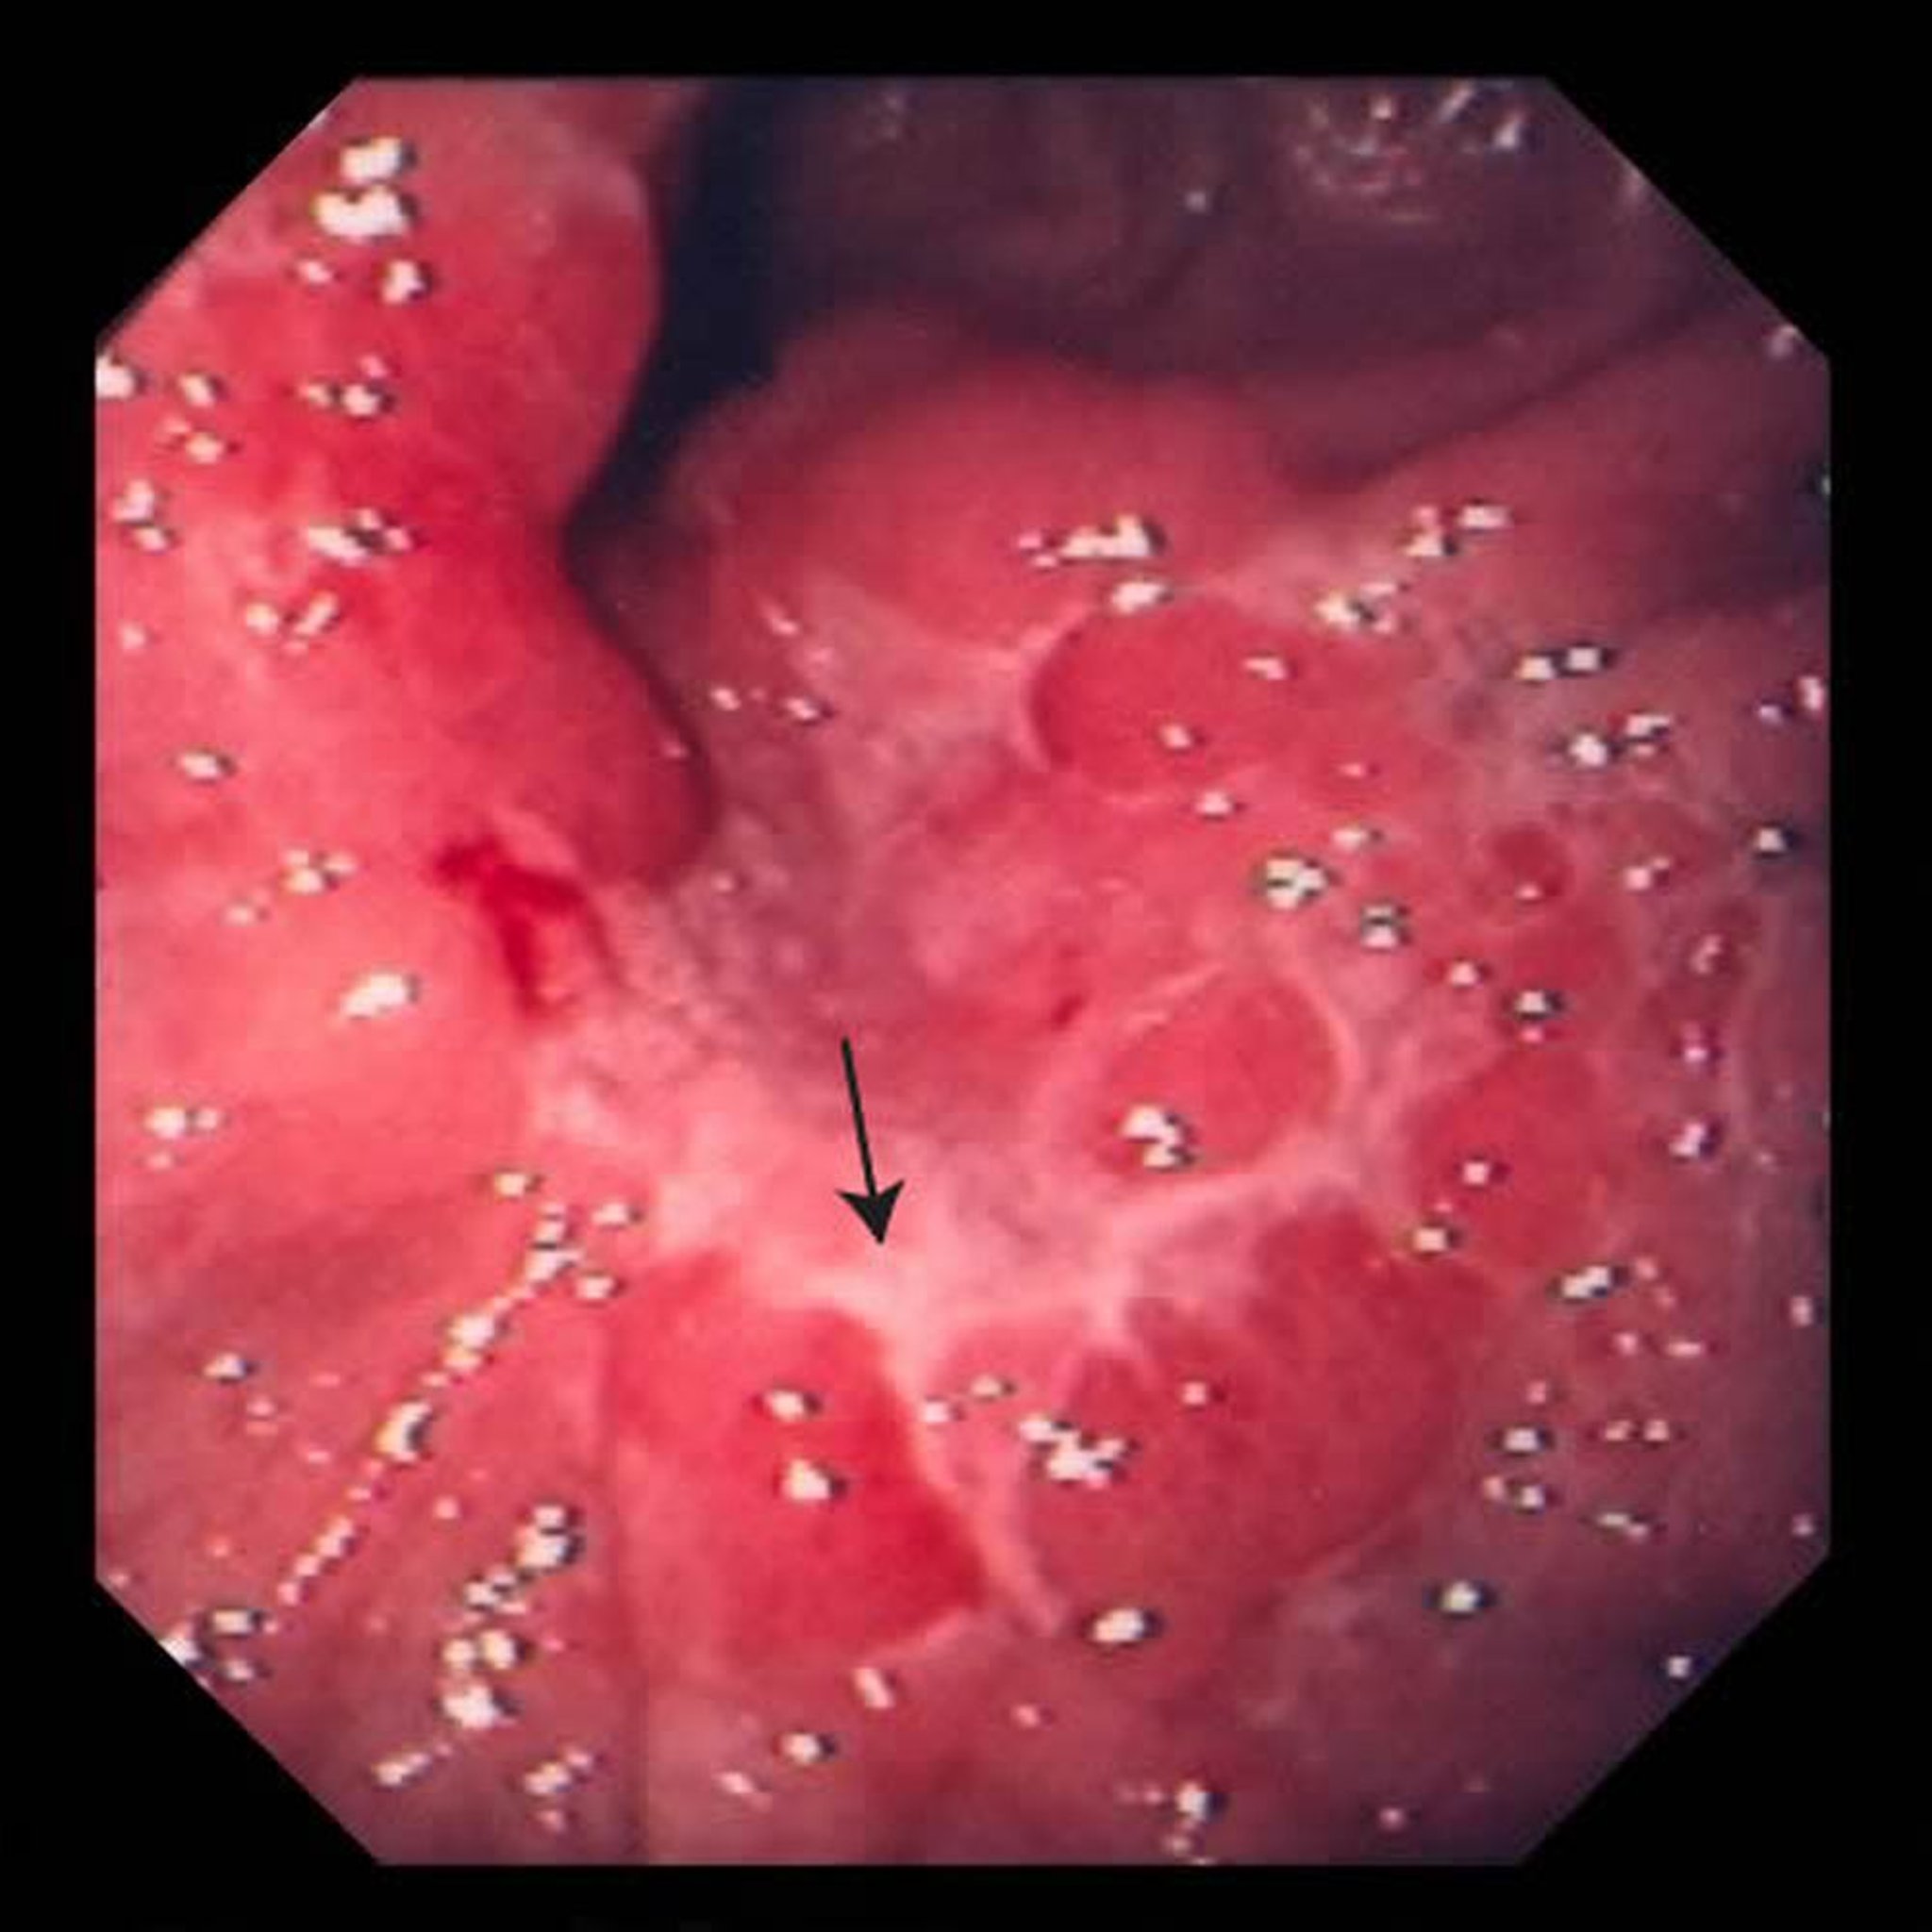

この画像には、胃に発生した潰瘍が写っています(矢印)。生検後に、腺がんと判定されました。

Image provided by David M.Martin, MD.